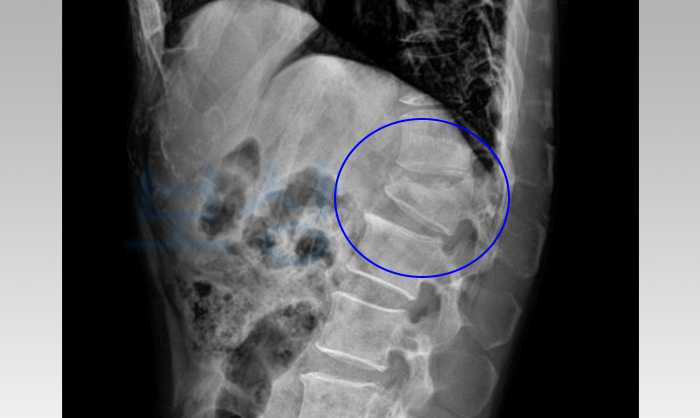

병 명: 요추1번 불안정성 방출성 골절

이 사고로 인해 허리골절을 당하셨는데 방출성 골절로서 허리뼈 골편이 뒤로 밀려서 이탈하는 심한 골절이었습니다. 자칫하다가 신경에 손상이 가게 되거나 마비 증상의 가능성까지 있기 때문에 수술을 통해서 치료를 진행하셨습니다.